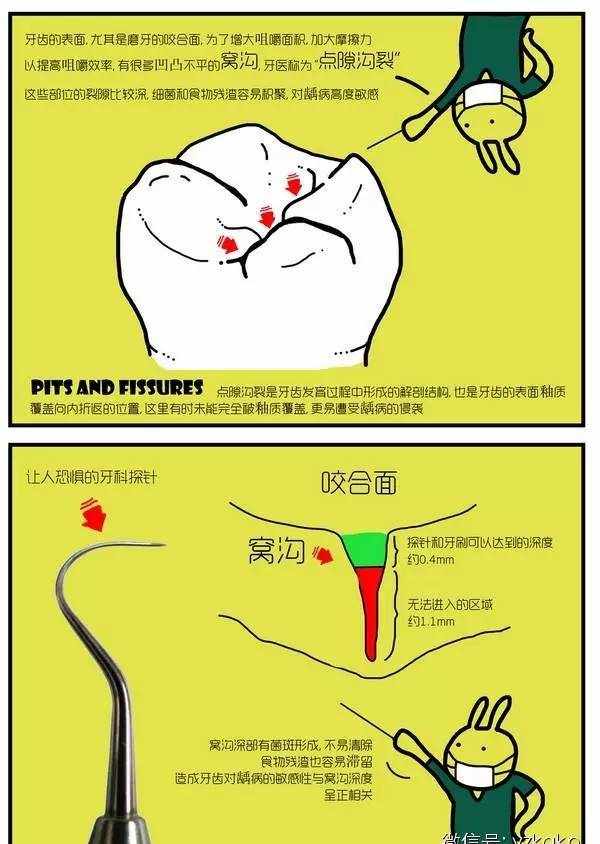

窝沟封闭又称点隙裂沟封闭(pit and fissure sealant),是指不去除咬合面牙体组织,在其上涂布一层粘结性树脂,保护牙釉质不受细菌及代谢产物侵蚀,增强牙齿抗龋能力,从而达到预防龋病发生的一种有效防龋方法。

1.为什么要进行窝沟封闭?

窝沟封闭最重要的作用就是可以避免发生龋齿。饮用水中的氟可以保护牙齿的光滑面,但后牙需要额外的保护。

窝沟封闭剂保护后牙咬合面上的细小窝沟,把食物和细菌隔绝在外。在牙齿龋坏以前给牙齿涂上封闭剂就能有效避免龋坏,从而大大地为患者节约了治疗时间和金钱。

而且,再看看牙齿表面这些深深的“藏身之处”,细菌套路这么深,牙刷也无力把它清扫干净啊。